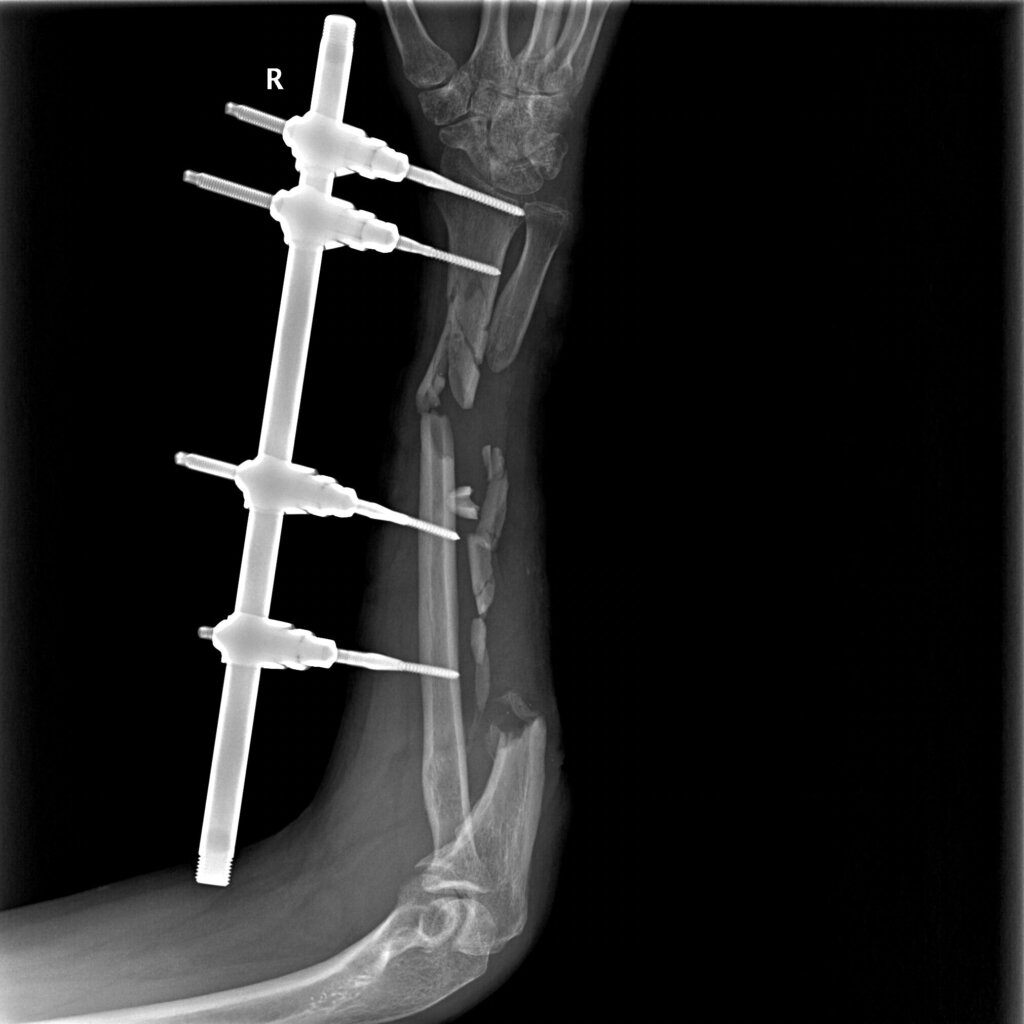

Согласно данным анамнеза и медицинской документации, пациент М. 49 лет получил огнестрельное осколочное ранение правой верхней конечности. Первая помощь оказана на месте. При поступлении в медицинский отряд пациенту выполнено рентгенологическое исследование правого предплечья. Выявлено: открытый многооскольчатый перелом нижней трети диафиза правой лучевой кости со смещением костных отломков, многооскольчатый перелом верхней и средней трети диафиза правой локтевой кости со смещением и дефектом костной ткани. Выполнена первичная хирургическая обработка ран правого предплечья и фиксация костей предплечья в АВФ КСВП1. На этапах эвакуации пациенту проводились этапные хирургические обработки до заживления ран предплечья.

На 5 сутки с момента поступления пациенту был выполнен демонтаж АВФ КСВП с правой верхней конечности, фиксация полимерной лонгетой от средней трети плеча до пястно-фаланговых суставов правой кисти.